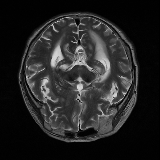

Brain Tumor Segmentation (BraTS 2019). In this task, we perform patient-wise two-fold cross-validation on the Brats-2019 training set. In each training fold, we use a 90/10 split after removing empty slices. The 2D slices from the 90% split without tumors are used to make our reference distribution ; while the 2D slices with tumors from the 90% split and all the slices from the 10% split are used for training our model. As a result, the sample size of for fold one and two amounts to 11,745 and 12,407 respectively, while the size of amounts to 11,364 and 10,786, respectively. We train this network using two cycles in the first stage and one cycle in the second stage.

We obtain a subject-wise mean Dice score of 63.67% for the brain tumor segmentation. Utilizing a simple post-processing scheme of erosion and dilation with filter, we improve our mean Dice score to 68.01%. Figure 4 shows samples generated by our ASC-Net and Table 2 shows our before and after post-processing results. We attempted to apply f-AnoGANs [34] by following their online instructions and failed to generate good reconstructions as shown in Figure 5. The failure of AnoGANs in the reconstruction brings to light the issue with the regeneration based methods and the complexity and stability of GAN-based image reconstruction.

A most recent work in [27] trains their algorithm using 1,112 healthy scans from the Human Connectome Project (HCP) young adult dataset [38] and tests on 50 random BraTS 2018 scans, obtaining a mean dice score of 67.2% and 15.5% standard deviation. Following our simple post-processing scheme, our algorithm performs better, increasing the mean Dice score by 0.81% and reducing the standard deviation by 0.97%, on two-fold cross validation across 335 scans. Another work in [42] tests on the BraTS 2018 training set, obtaining a mean dice score of 71.63% and standard deviation of 0.84%. While their method outperforms ours, it is worth to mention that the self-supervised method is highly specialized to a particular task of tumor segmentation. It may happen that the object to be segmented is difficult to synthesize artificially or perfectly, resulting in a bottleneck of the pipeline. Furthermore, one assumption of a self-supervised learning algorithm is that the object to be learnt is known beforehand. Thus, a model trained for brain tumors cannot be applied readily to other anomalies, e.g., brain lesions. Our method, on the other hand, has no such limitations and does not need Pseudo dataset generation for a new task. That is, our method is a general approach for anomaly detection and segmentation. Also, our method performs better than [42] on the liver lesion segmentation task after post-processing.